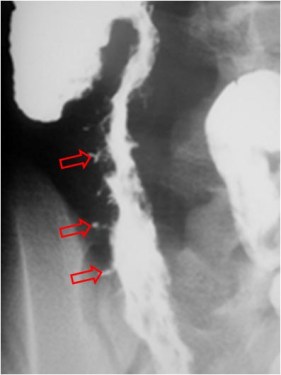

SIGNO DEL PSEUDOTUMOR

En la radiografía simple de abdomen, cuando un asa intestinal está obstruida por un vólvulo se llena de líquido y produce una falsa imagen de masa con densidad de partes blandas (flechas) que no debe confundirse con un tumor.

Este signo debe diferenciarse de las asas rellenas de líquido en la obstrucción mecánica simple. En la obstrucción en asa cerrada, la presencia del signo del pseudotumor indica que un asa intestinal se encuentra fija y permanece en la misma posición en todas las proyecciones.

En la imagen, pseudomasa causada por asas distendidas, con líquido, en la obstrucción intestinal.